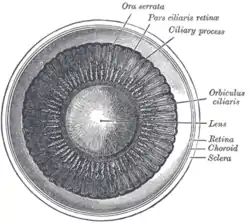

Interior of anterior half of bulb of eye. (Choroid labeled at right, second from the bottom.) | |

Schematic cross section of the human eye; choroid is shown in purple.

Schematic cross section of the human eye; choroid is shown in purple. Laser Doppler imaging of retinal and choroidal blood flow